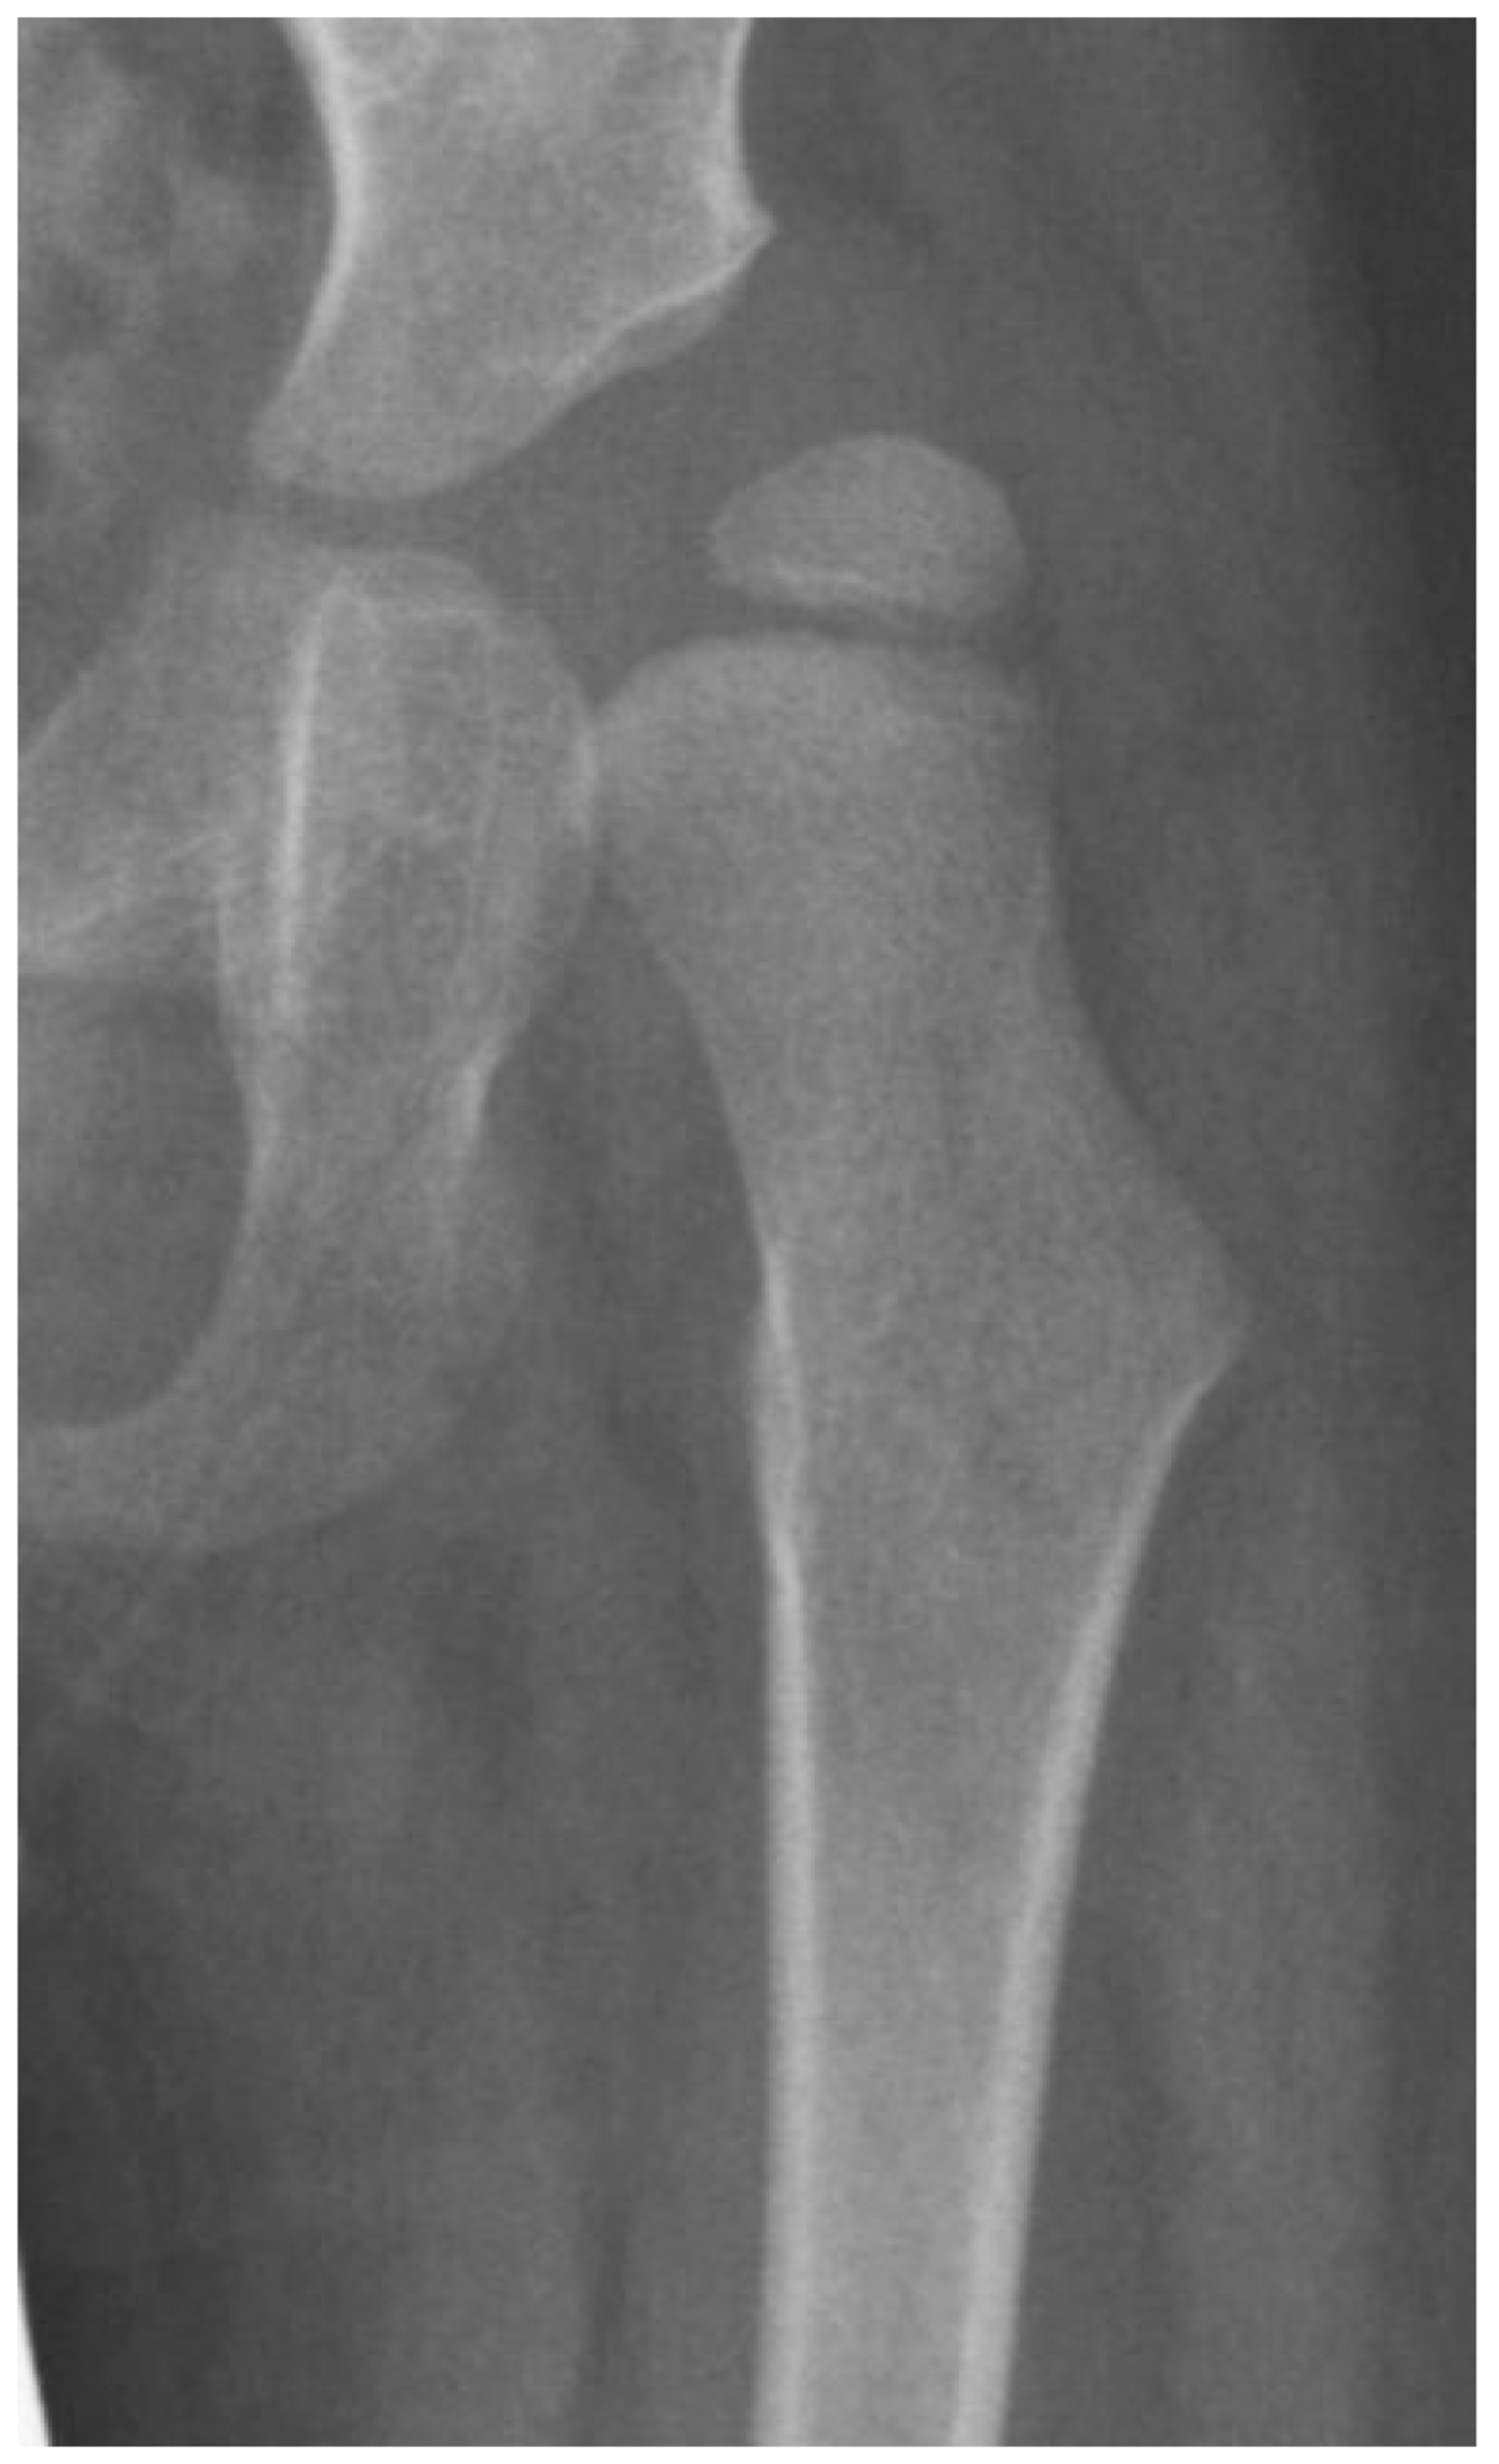

3.4.2. Pathologic Role of Coxa Valga and the Impact of its Correction on Spastic Hips

4.1.2. Pathologic Role of Coxa Valga and the Impact of its Correction in Weak and Hypotonic Hips

4.1.3. Pathologic Role of Coxa Valga and Treatment Options in Paralytic Hips